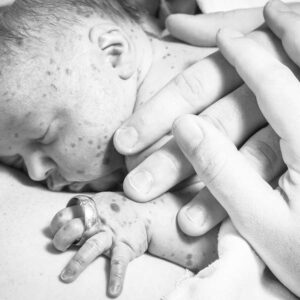

My son was delivered by emergency c-section. The first glimpse I had of him, I noticed he was blue, and his skin was covered with deep purple spots. He wasn’t crying. The whole room was especially quiet. I thought the worst, my heart dropped, but then – he let out the weakest cry. Thank God, he was breathing.

I saw him only by glance as they rushed him to the NICU. I told my husband to stay with him and that I would be fine. My husband went, and I was alone, cut apart, medicated and anxiously terrified. The surgical team sewed me up and I was taken to my room. I willed my legs awake from the spinal tap, like Uma Thurman in Kill Bill, and then I physically dragged myself from my bed to a wheelchair to see him. I demanded a nurse take me to him. When I got there I could hardly see him under all the wires and tapes. He wasn’t even that small for being 7 weeks premature, weighing in at 6.3lbs, but they had no clue what was going on – so every possibly machine was hooked up.

Dominic was out of acute danger but he needed time to heal his body. We had biopsies on his skin and found that his spots are just benign birthmarks – yet so many more than any of our doctors had seen before. The amount of birthmarks was shocking and the dermatologist was involved daily to make sure her diagnosis was correct. There was a possibility of it being an ever rarer condition, but a skin biopsy confirmed they were just birthmarks. We reached out to specialists across the world and none of them had seen a case like Dominic’s. He had many issues with the birthmarks; he would bleed from several of them daily and required transfusions. We also found out he had a brand new genetic mutation. He may be the only one in the world that has this mutation.